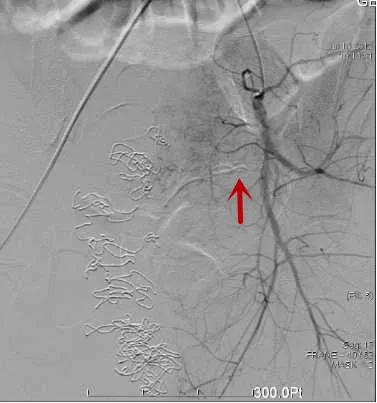

△造影找到出血动脉/找到出血责任动脉/精准栓塞后出血动脉已闭塞